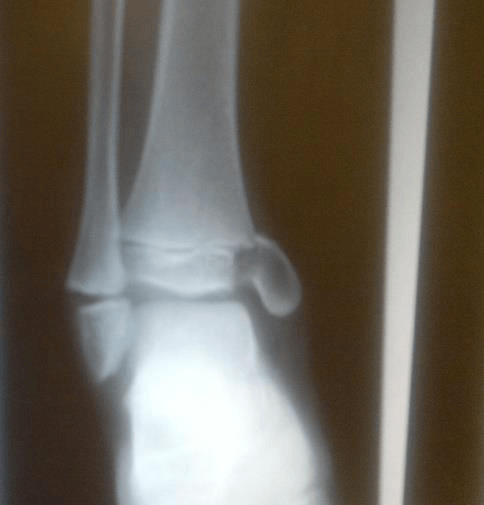

A five-month-old boy is taken to the emergency department with swollen, bruised right ankle.

His x-ray is shown below.

Which of the following is the most likely diagnosis?

A. Non-accidental injury

B. Septic arthritis

C. Osteosarcoma

D. Rickets

E. Congenital club foot

A Non accidental injury